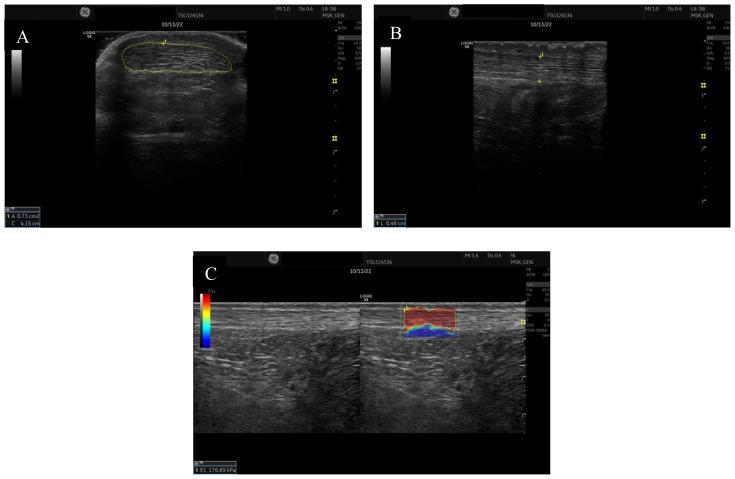

Morphologic Achilles tendon properties obtained via diagnostic ultrasound imaging are valuable in understanding Achilles tendon health and injury. Currently, limited information exists regarding Achilles tendon morphological properties amongst active aging adults based upon Victorian Institute of Sport Assessment (VISA-A) scores. Achilles tendon morphologic properties defined by VISA-A score groupings allow clinicians and researchers to compare data values amongst current patients. Purpose: Comparison of physically active aging adults Achilles tendon morphological properties with various VISA-A scores or a previous Achilles tendon rupture. A convenience sample of 121 participants (71 females, 50 males) at least moderately active and 50 years old, were recruited. Participants completed a VISA-A survey, and assigned groups by scores (Group 1: 90-100, Group 2: 70-89, Group 3: 45-69, Group 4: Previous Achilles tendon tear). Achilles tendon ultrasound imaging occurred at the malleolar line (The apex of the medial and lateral malleolus). Following imaging Achilles tendon cross-sectional area (CSA), thickness, and elastography were measured and analyzed. Participants with a previous Achilles tendon rupture displayed significantly larger tendon CSA and thickness compared with other groups (p<0.05). Individuals with VISA-A scores from 45-69 displayed significantly larger tendon CSA and thickness than participants with scores greater than 90 (p<0.03). No significant differences were noted for elastography between groups (p>0.05). Achilles tendon morphological differences exist based upon pain level in physically active aging adults. Diagnostic ultrasound may be used during assessment and rehabilitation of injured tendon tissue to inform about current tendon tissue properties.

通过诊断超声成像获得的跟腱形态学特性,对于理解跟腱健康状况和损伤情况具有重要价值。目前,基于维多利亚运动评估机构(VISA - A)评分,关于活跃的老龄成年人跟腱形态学特性的信息有限。根据VISA - A评分分组定义的跟腱形态学特性,使临床医生和研究人员能够比较当前患者的数据值。目的:比较身体活跃的老龄成年人在不同VISA - A评分或既往有跟腱断裂情况下的跟腱形态学特性。招募了121名至少中度活跃且年龄在50岁及以上的参与者(71名女性,50名男性)作为便利样本。参与者完成了VISA - A调查问卷,并根据得分分组(第1组:90 - 100分,第2组:70 - 89分,第3组:45 - 69分,第4组:既往有跟腱撕裂)。在踝关节线(内、外踝顶点)处进行跟腱超声成像。成像后测量并分析跟腱的横截面积(CSA)、厚度和弹性成像。既往有跟腱断裂的参与者与其他组相比,显示出明显更大的肌腱CSA和厚度(p<0.05)。VISA - A评分为45 - 69分的个体,其肌腱CSA和厚度明显大于得分高于90分的参与者(p<0.03)。各组之间在弹性成像方面未观察到显著差异(p>0.05)。身体活跃的老龄成年人的跟腱形态学差异基于疼痛程度而存在。在评估和康复受伤的肌腱组织时,可使用诊断超声来了解当前肌腱组织的特性。